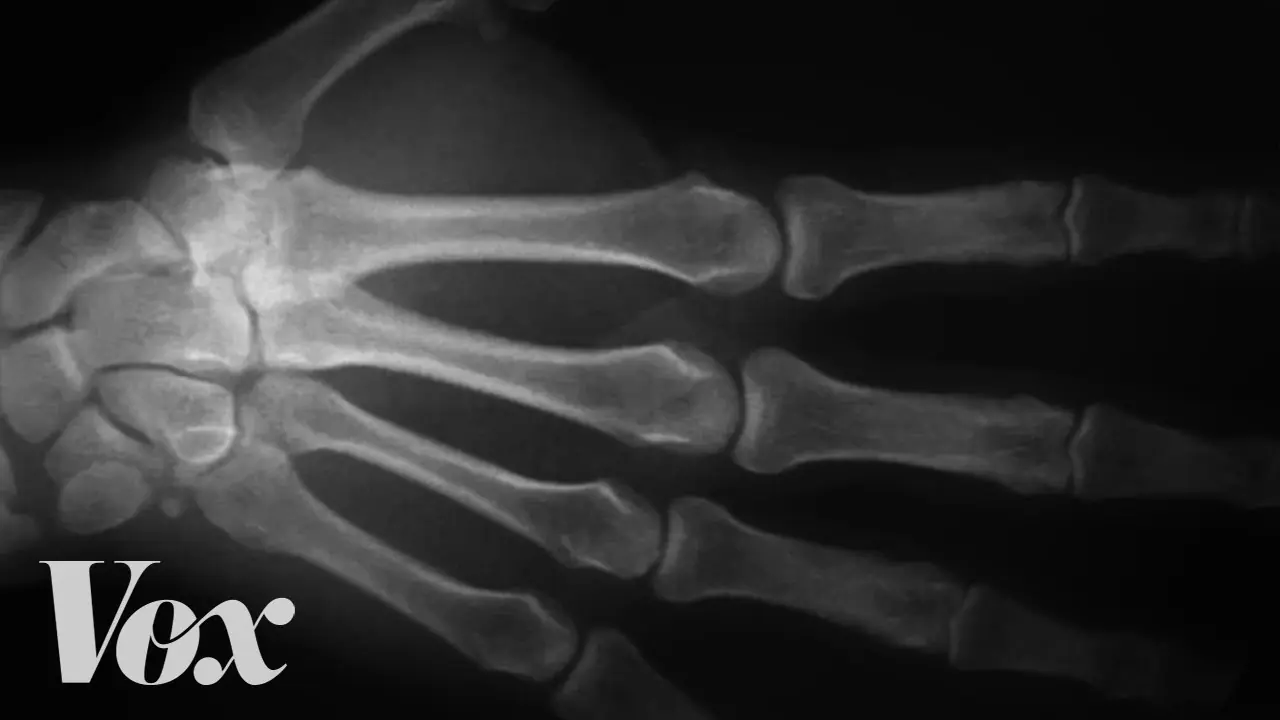

Simulation Explains What Really Happens When You Crack Your Knuckles